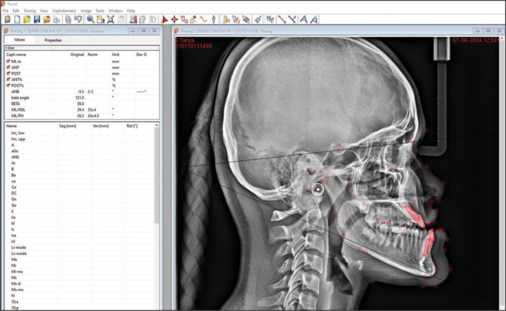

Materials and methods: CBCT images of 84 patients were collected for the study. FACAD (ILEXIS AB, Linköping, Sweden) software was used to divide the patients into Class I, II, and III skeletal malocclusions. Dolphin software was used to measure the width, length, and height of condyles and glenoid fossa of the patients from the CBCT images. The Shapiro-Wilk test was used to check normality. ANOVA test was performed to assess the statistical significance of the results between the 3 groups.